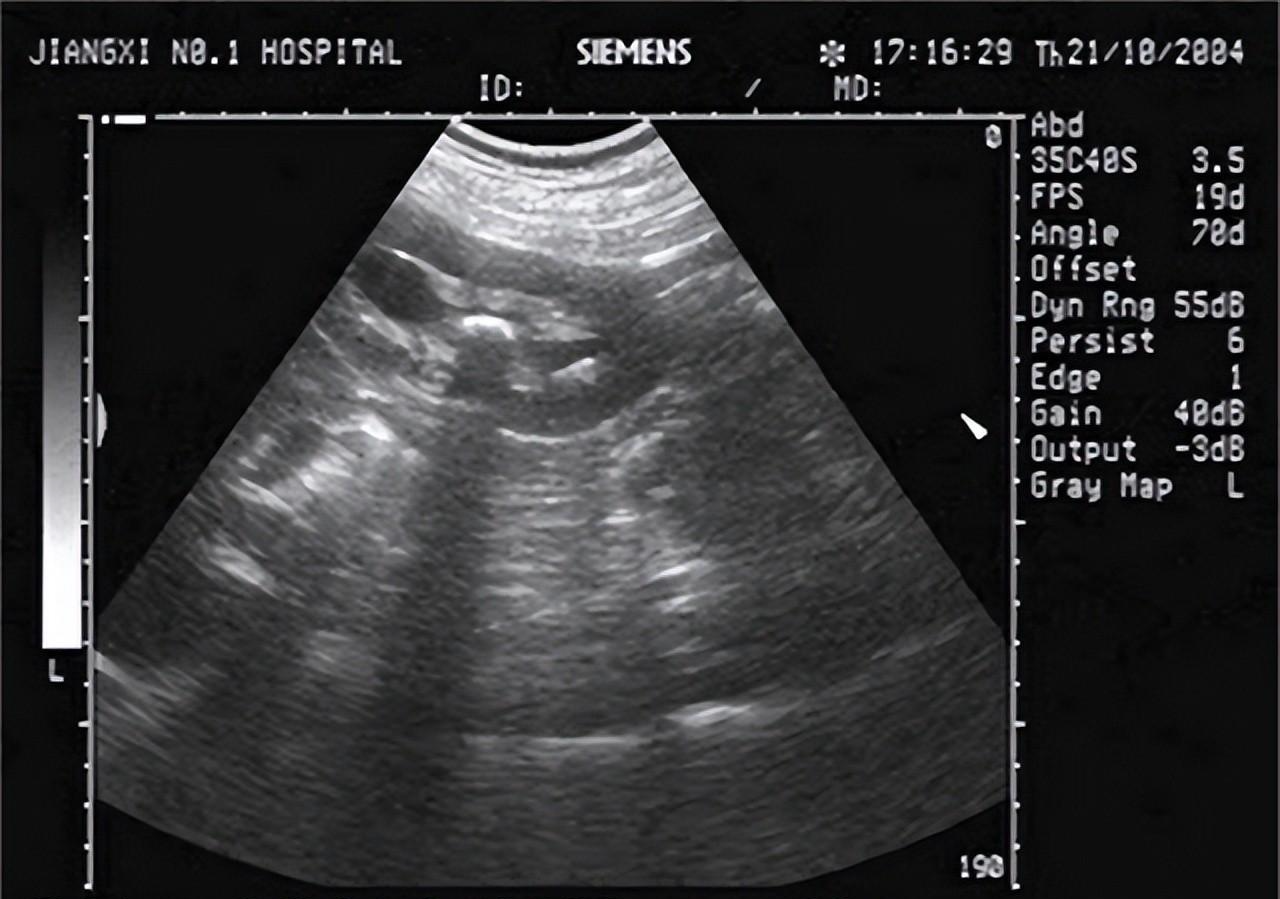

医生听完李大爷的自述 , 盯着那瓶降压药看了半天 , 上面赫然写着苯磺酸氨氯地平片 , 便连忙安排让李大爷去做尿常规检查还有肾脏B超检查 , 检查结果一出来 , 医生就对李大爷说道:您这是擅自换降压药导致的肾衰竭 , 幸亏就医早 , 不然后果不堪设想 。 您看 , 您的尿蛋白都三个加号了 , 还有尿肌酐值也到150umol/L了 , 肾脏B超也提示双肾体积减小 , 再联系您最近的临床症状 , 这就是肾衰 。